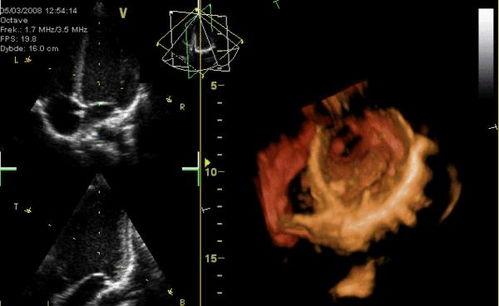

你知道吗,心脏跳动其实是一种非常复杂的生理现象。它是由心脏的肌肉组织自动收缩和舒张产生的。而心脏跳动视频,就是通过高科技手段捕捉到的心脏跳动画面。这些视频通常是通过医学影像技术,如超声心动图、心电图等设备拍摄而成的。

心脏跳动视频不仅能够展示心脏的跳动过程,还能让我们直观地看到心脏的结构和功能。比如,通过心脏跳动视频,我们可以看到心脏瓣膜的开关、心室的收缩与舒张等。这些信息对于心脏疾病的诊断和治疗具有重要意义。